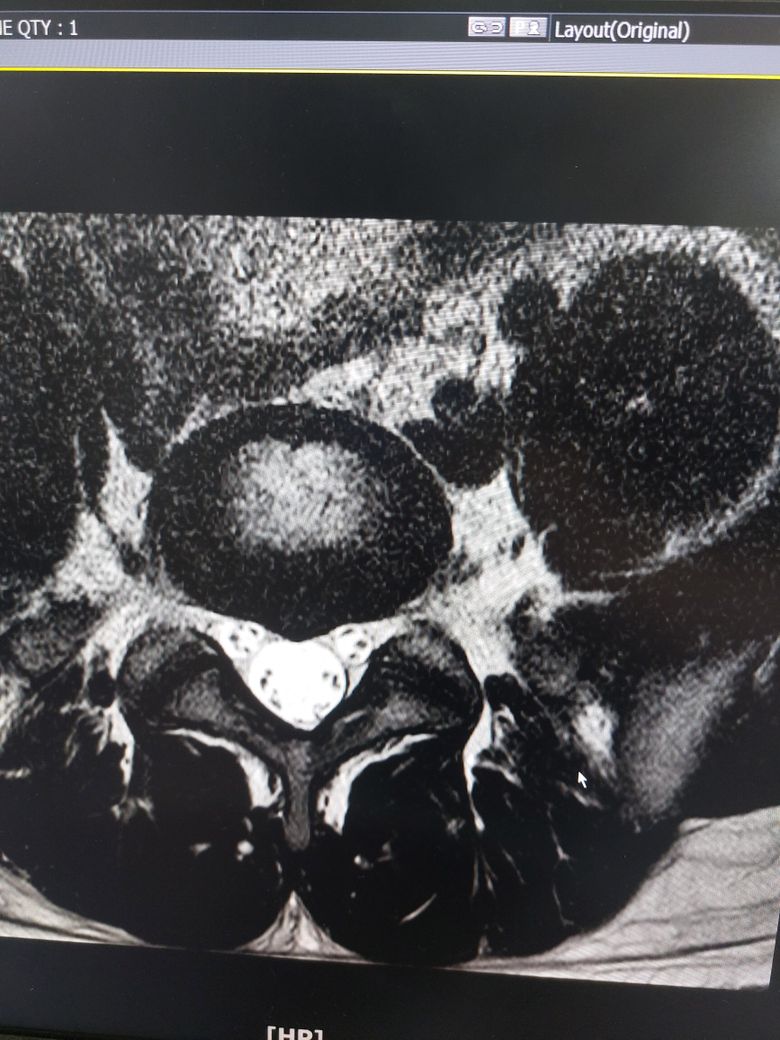

사진은 제 mri입니다